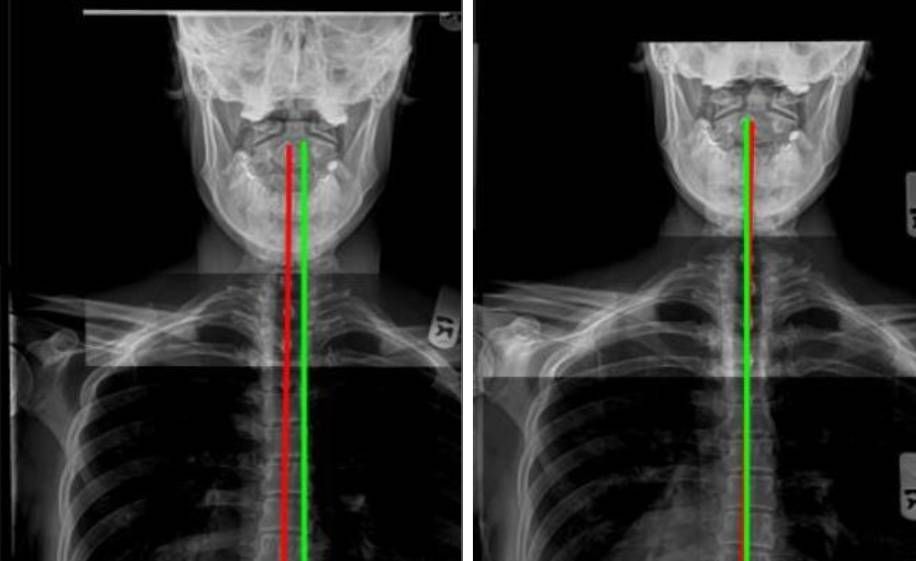

Good posture refers to the correct alignment of your body, while you’re standing, sitting, or lying down. Proper alignment of your body puts the least amount of strain on your muscles and ligaments and requires muscle strength and flexibility, joint mobility, and the right balance of postural on both sides of your spine. Your spine is the housing system of the spinal cord and the nervous system which is the electrical circuit of your entire body that controls the functions of organs, hormones, and the immune system.

Poor posture habits can develop over time, creating neuromusculoskeletal imbalances that affect your overall health and wellbeing. With posture correction at Loudoun Ideal Chiropractic, Dr. Miok helps you become more aware of your posture habits and designs a program to reestablish a better alignment in your spine to restore and strengthen the nervous system in your body.

- Posture and spine evaluation and necessary x-rays

- Individualized safe Yoga Poses and Stretches and core strengthening based on your spinal x-ray